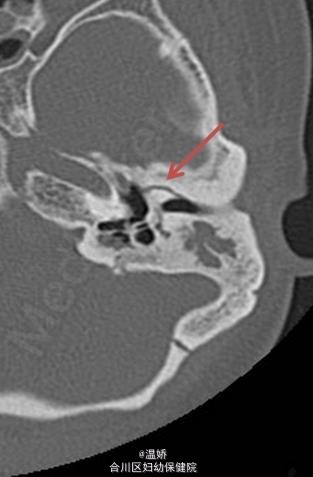

伴先天性耳畸形的范可尼贫血患者 1 例

先天性耳畸形

患者,女性,25 岁,范可尼贫血伴听力丧失。